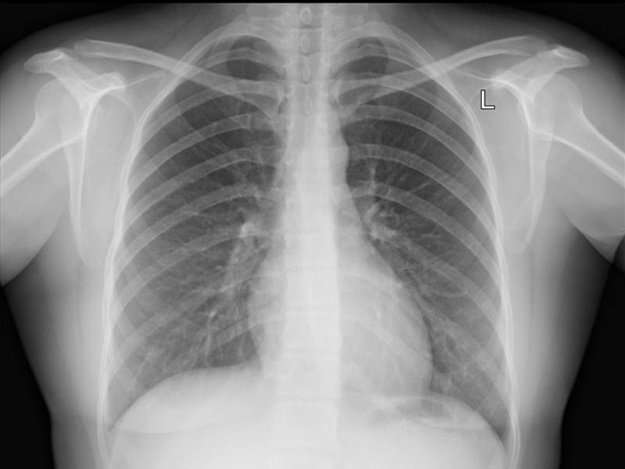

Правосторонняя пневмония.

Возможна с имитацией приступа аппендицита, боль под ребрами, возникающая при вдохе и кашле без четкой локализации и сопровождающаяся повышенной температурой, а при движении возникает одышка.

Сухой плеврит.

Возникает при легочных патологиях, боль слева и справа под ребрами, усиливается при дыхательных и обычных движениях, отдающая в спину, сопровождается учащенным дыханием и периферическим цианозом.

Патологии дыхательных органов

Если у человека болит ближе к спине, в области поясницы, то у него могут быть патологии дыхательной системы. Он может болеть:

- Плевритом.

- Воспалением легких.

- Пневмотораксом.

- Раком бронхов, легких.

При дыхательных патологиях боли могут проявляться несильно, но со временем их интенсивность нарастает. Зачастую пациент жалуется на болезненность во время движения, хрипы в легочных тканях, режущий болевой синдром под левым ребром, который усилится во время кашля. Болевой синдром может усилиться во время вдоха, когда больной выдыхает, то боль уменьшается. Частые боли свидетельствуют об онкологических процессах с метастазами к соседним органам, тканям, с образованием больших некротических очагов.